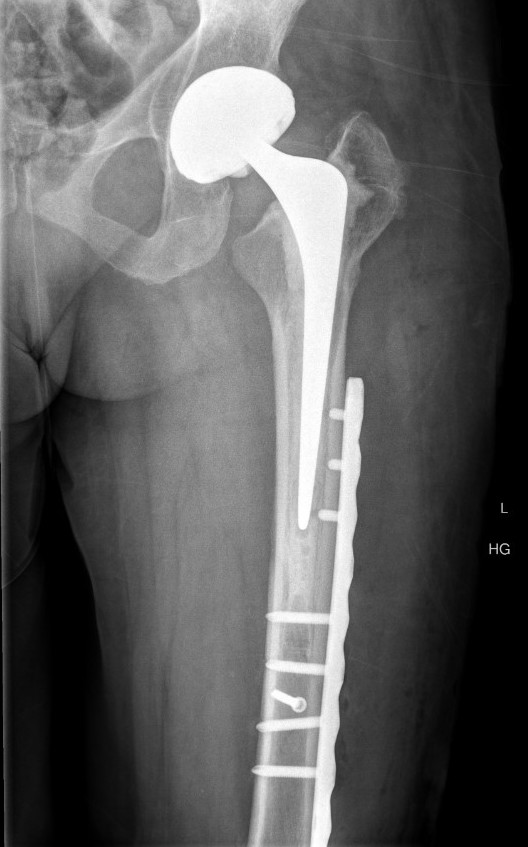

Type B1: Fracture around stem, likely well fixed

Management

ORIF with locking cable plate and +/- Cortical strut allograft

Plates

Contoured anatomical fit with trochanteric extension

Variable angle locking screws to go around implants

Cable options

Unicortical screw options

Revision uncemented arthroplasty with Zimmer cable plate